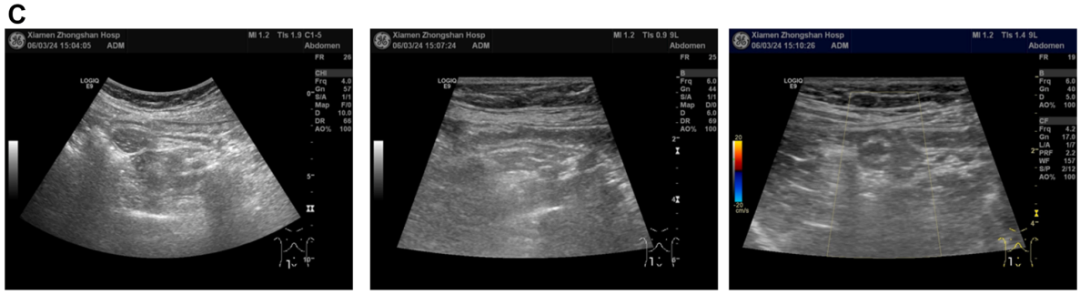

病史摘要:患者为 49 岁女性,因“反复胃肠道息肉切除 17 年余,腹胀 3 天”入院。既往有多部位囊肿,曾行右侧颈部神经鞘瘤手术。家族中父亲、两个哥哥均有结肠息肉相关病史。2008 年首次发现胃底、胃体、结肠等多发性息肉,病理为胃底腺瘤性息肉,此后多次行胃肠镜检查及内镜下息肉切除术。 诊疗过程:入院查体生命体征平稳,慢性病容,上腹轻压痛。2019 年基因检测提示 A